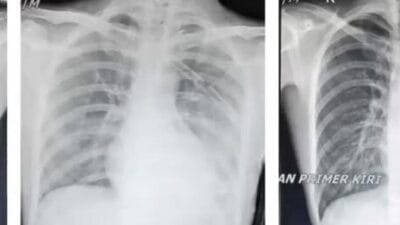

RADARINDO.co.id : Rokok konvensional dan vape sama-sama mengandung bahan karsinogen dan bahan oksidatif (radikal bebas)…